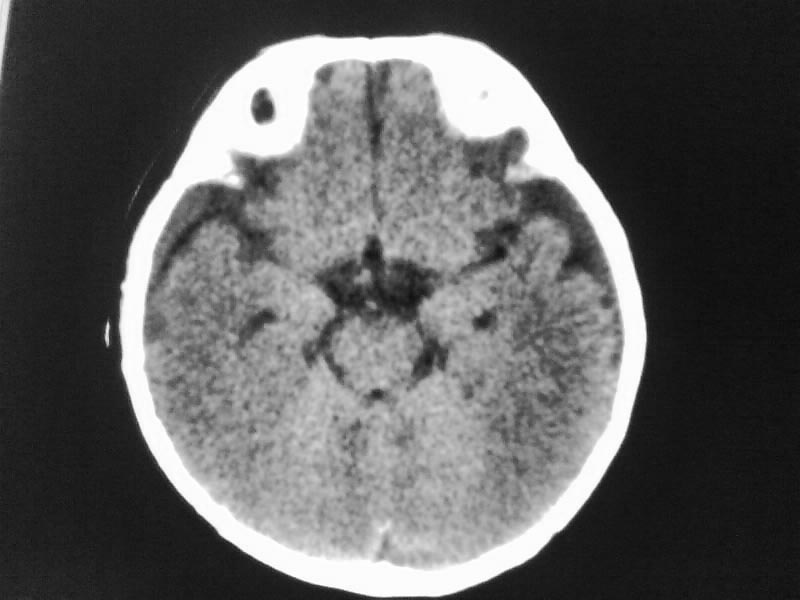

以下是引用随光逐影在2009-4-15 17:59:00的发言:[br]1)右侧额颞顶部硬膜下血肿。2)外部性脑积水。